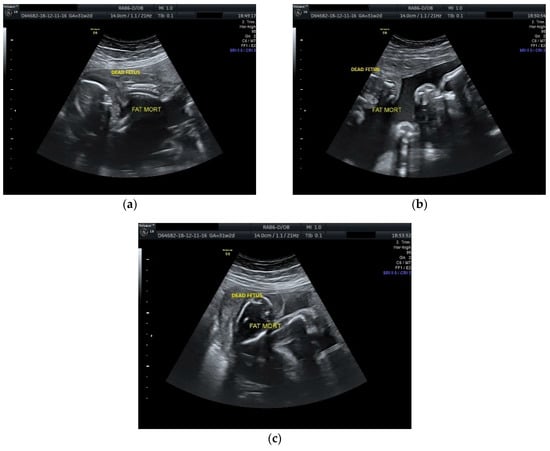

The case was managed conservatively with regular monitoring of the maternal coagulation profile, along with intensive fetal surveillance for the surviving twin (Figure 2 and Figure 3).

Figure 2.

Ultrasound scan performed at 29 weeks and 1 day of gestation: (a), (b) dead fetus along with normal growing fetus with normal amniotic fluid; (c) cephalic extremities of the two fetuses with evident growth discordance.

Figure 3.

Ultrasound scan performed at 31 weeks and 2 days of gestation: (a), (b), (c) dead fetus with consistent plastic changes along with normal growing fetus with normal amniotic fluid.